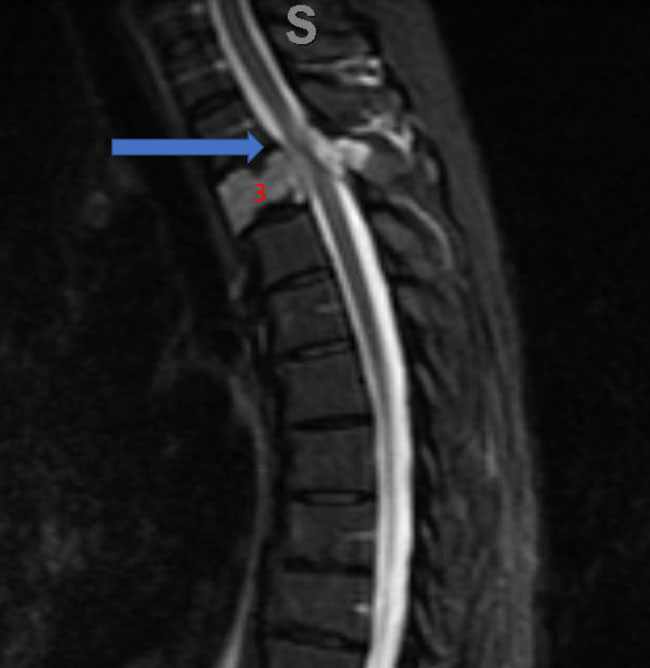

Figure 1. A) Sagittal T2 MRI demonstrates aggressive hyperintense T3 hemangioma involving the body and posterior elements compressing the thoracic spinal cord (arrows)

Figure 1. B and C) Axial MRI images of T3 demonstrates extensive infiltrative lesion with extradural compression of the thoracic spinal cord. (Dashed lines in A) tumor infiltration; Dashed lines and Arrows in B) cord compression.

He presented to the emergency room with one-week history of thoracic pain in addition to bilateral lower extremity weakness and paraparesis. MRI imaging with contrast showed a diffuse abnormal signal within the vertebral body of T3 and the posterior elements with lobulated soft tissue lesion extension into both paraspinal areas (Figure 1. A, B, C).